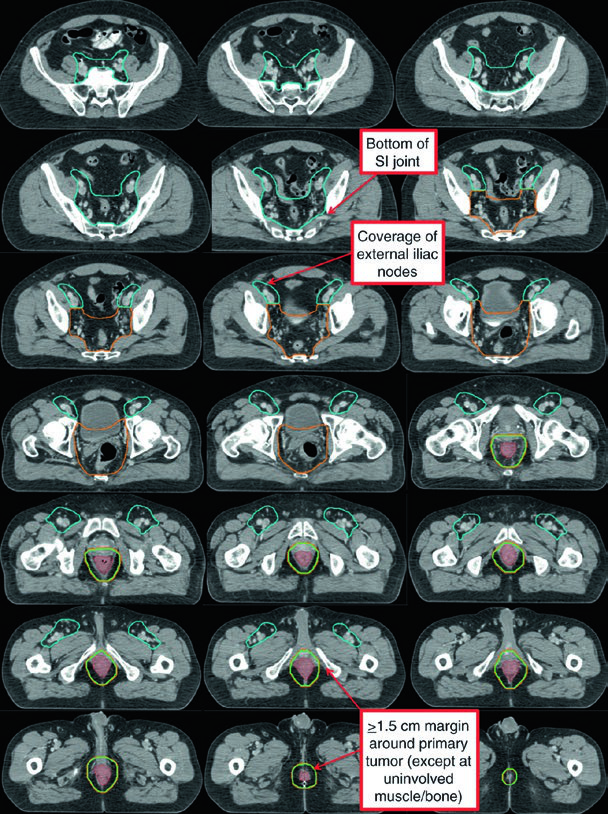

| CTV-P, CTV-N | CTV-P: GTV-P + margem de 1,5–2,5 cm excluindo osso, músculo ou ar não envolvidos. CTV-N: GTV-N + 1,0–1,5 cm excluindo osso, músculo ou ar |

| CTV-HR (alto risco) | Cobre CTV-P, CTV-N, mesorreto inteiro, linfonodos perirretais e ilíacos internos bilaterais inferiores à borda inferior da articulação sacroilíaca. Se inguinais ou ilíacos externos envolvidos, incluí-los. Margem de 0,7 cm ao redor dos vasos ilíacos internos. Margem de 1,8 cm entre vasos ilíacos externos e internos para obturadores. Margem de 1–1,5 cm na bexiga anteriormente |

| CTV-LR (baixo risco) | Cobre linfonodos ilíacos internos não envolvidos superiores à borda inferior da articulação sacroilíaca, ilíacos externos e inguinais não envolvidos. Margens: 0,7 cm ao redor dos vasos ilíacos internos; 1 cm anterolateral nos ilíacos externos; contorno do compartimento inguinal completo |

| PTV | Expansão de 0,5–1 cm de cada CTV, dependendo da acurácia de setup, frequência de imagem e uso de IGRT |

Atlas de Contorno: Regiões Nodais Eletivas

O atlas de contorno anorretal do RTOG descreve três regiões CTV que devem ser incluídas para todos os pacientes com câncer de canal anal. O Australasian GI Trials Group Atlas detalha sete regiões eletivas. Há desacordos entre as diretrizes RTOG, AGITG e BNG quanto ao contorno dos linfonodos inguinais — dados recentes mostram que 10–29% dos linfonodos inguinais envolvidos ficam fora das bordas nodais recomendadas.

| CTV-A (perirretais, pré-sacrais, ilíacos internos) | Pelve inferior: borda inferior 2 cm abaixo da doença macroscópica, incluindo mesorreto inteiro. Pelve média: reto, mesorreto, ilíacos internos, margem de 1 cm na bexiga. Pelve superior: até bifurcação das ilíacas comuns (~promontório sacral). Margem de 7–8 mm nos vasos ilíacos internos |

| CTV-B (ilíacos externos) | Fronteira entre inguinal e ilíaco externo na extensão inferior dos vasos obturadores internos (borda superior dos ramos púbicos superiores). Margem de 7–8 mm, ao menos 1 cm anteriormente |

| CTV-C (inguinais) | Extensão inferior 2 cm abaixo da junção safeno-femoral. Contornar compartimento inguinal inteiro incluindo pequenos vasos e linfonodos |

O caso T2N0 demonstra quimorradioterapia definitiva com IMRT: PTV-LR e PTV-HR tratados simultaneamente a 40 Gy (1,6 Gy/fração) e 45 Gy (1,8 Gy/fração) em 25 frações, respectivamente. Depois, o PTV-P recebeu boost sequencial a 50,4 Gy (1,8 Gy/fração) em 28 frações totais.

No caso T3N1a com envolvimento inguinal bilateral, PTV-LR e PTV-HR foram tratados simultaneamente a 40 Gy e 45 Gy em 25 frações. Os linfonodos inguinais e ilíacos externos bilaterais foram incluídos no CTV-HR por causa do envolvimento bilateral. Depois, PTV-P e PTV-N receberam boost a 54 Gy em 30 frações totais.